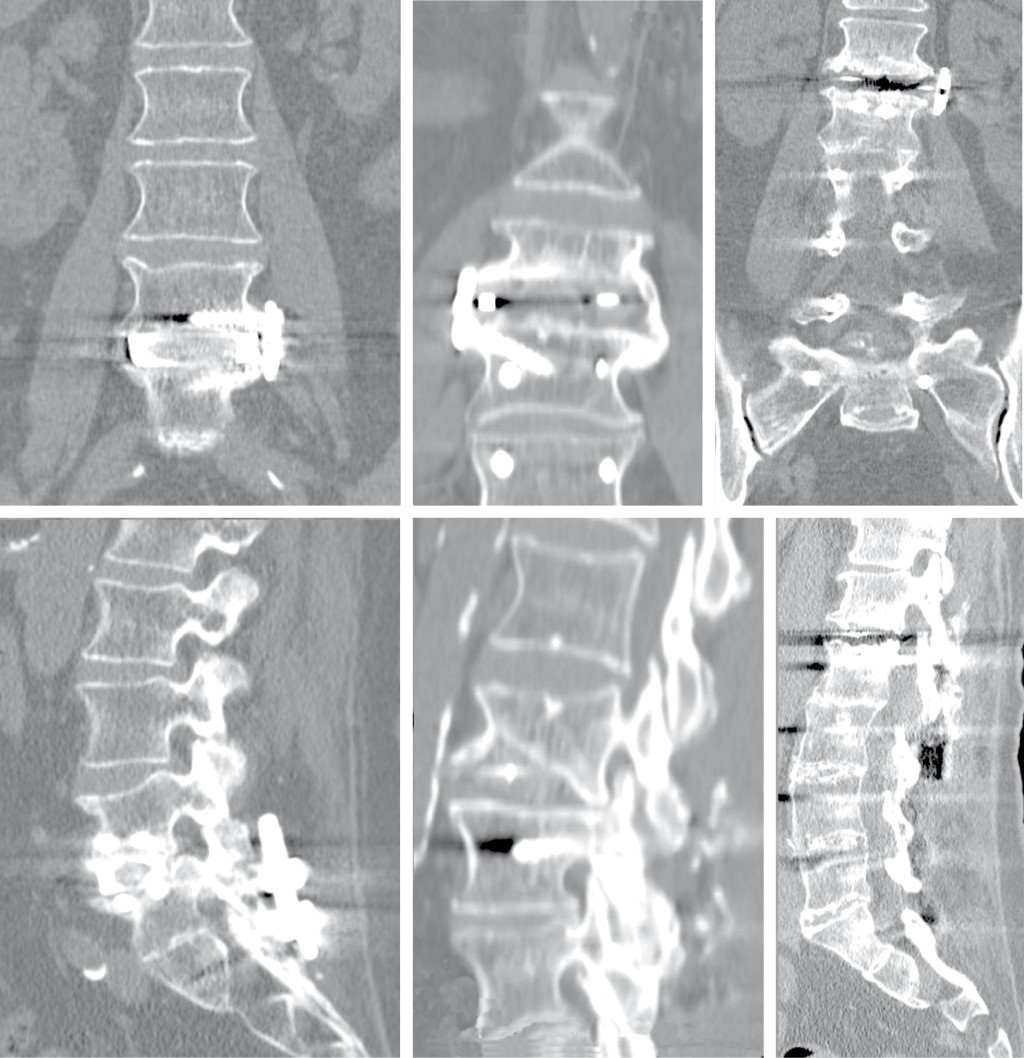

Las variables postquirúrgicas (resultados clínicos, de calidad de vida y los parámetros radiológicos) se recogieron tras la cirugía al primer, sexto y décimo segundo mes. Se realizó TC lumbar al año de la inntervención en búsqueda de tasa fusión, distinguiendo: fusión completa (formación de puentes óseos a través y alrededor del implante), fusión incompleta (puentes óseos a través o alrededor del implante) y falta de fusión (seudoartrosis) (Figura 2).23 Se registraron todas las complicaciones locales y sistémicas, intraoperatorias y postoperatorias durante el período hospitalario y durante el seguimiento. A su vez en cada grupo se distinguieron las complicaciones menores (recibieron tratamiento médico para su curación) y mayores (precisaron tratamiento quirúrgico para su resolución).

Figura 2